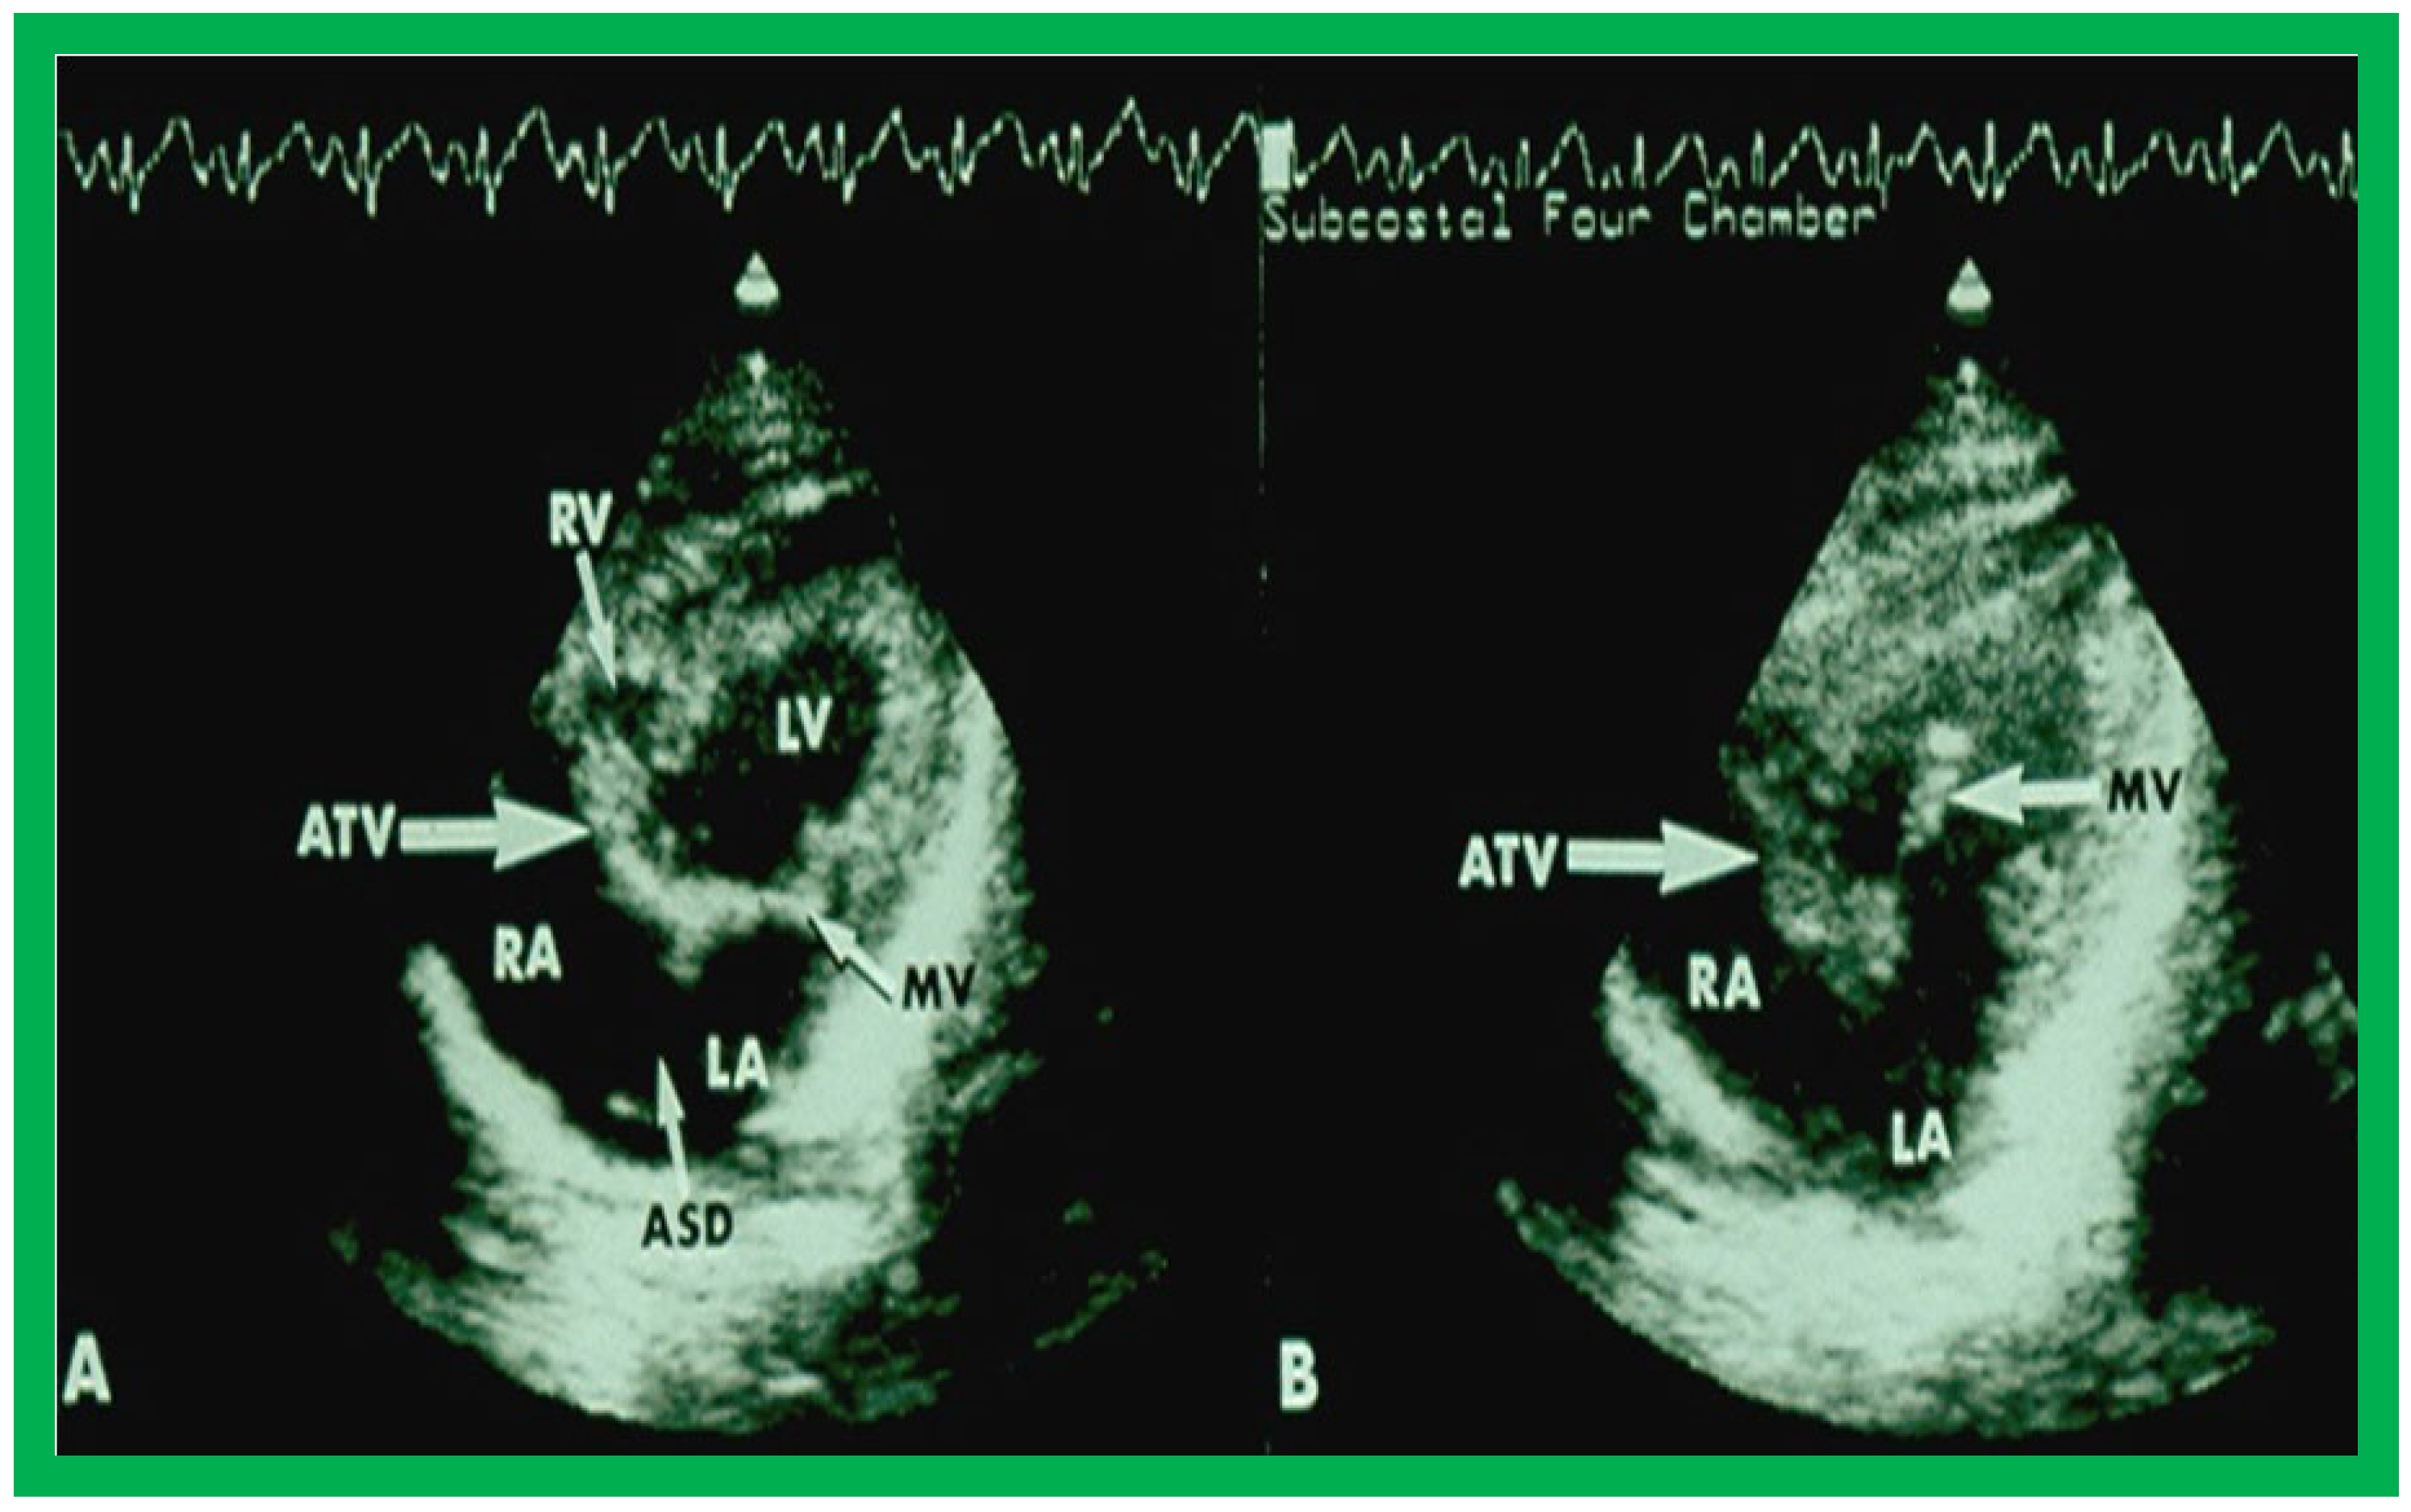

On 2D echocardiography, the atretic tricuspid valve is visualized directly as a dense band of echoes at the site where the tricuspid valve should be, as shown in Figure 4, Figure 5 and Figure 6; this echo appearance is that of the most frequent muscular type of TA. This anatomy is better demonstrated in apical and subcostal four chamber views than in other views. The other anatomic types (Figure 1), namely, membranous, valvular, Ebstein’s, atrioventricular septal defect, and unguarded tricuspid valve with muscular shelf, are rare and may also be recognized on 2D echocardiography. An example of an atrioventricular septal defect type of TA [30] is demonstrated in Figure 7; in this example, a 2D echocardiogram demonstrated an ostium primum ASD with a common atrioventricular valve and a small RV (Figure 7a,b); the entry into the RV appeared to be occluded by a leaflet of the common atrioventricular valve. Left ventricular and right atrial cineangiograms confirmed these findings [30]. Evaluation of the crux cordis (Figure 8) on a 2D echocardiogram (subcostal four chamber view) may help to distinguish the various anatomic types (Figure 1) from each other. In the muscular type of tricuspid atresia, a dense band of echoes is seen where the normal tricuspid valve should be (Figure 8A). In membranous types of tricuspid atresia, a thin membrane is seen instead (Figure 8B). In both these types, the anterior leaflet of the detectable atrioventricular valve is attached to the left side of the interatrial septum (Figure 8A,B). In the atrioventricular septal defect type of tricuspid atresia, the crux cordis is abnormal and cannot be identified; the anterior leaflet of the detectable atrioventricular defect is attached to the anterior wall of the heart, and a large atrioventricular valve leaflet occludes the entry of the RA into the RV (Figure 8C). Based on these observations, it was concluded that 2D echocardiographic (and angiographic) features help to differentiate the atrioventricular canal type of tricuspid atresia from the classic muscular tricuspid atresia cases [30].

Figure 5. Apical four chamber view pictures of an infant with tricuspid atresia with ostium primum atrial septal defect (large arrow in the middle of (B)). Note the small right ventricle (RV) and a ventricular septal defect (small arrow in (A,B)). LA, left atrium; LV, left ventricle; RA, right atrium. Reproduced from Reference [28].